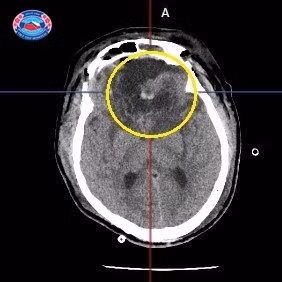

Người bệnh vào viện với tình trạng đau đầu, chóng mặt, buồn nôn. Trước đó, người bệnh chưa phát hiện bệnh mạn tính cũng như tiền sử gia đình khỏe mạnh. Sau khi được thực hiện các xét nghiệm lâm sàng cần thiết, chụp cắt lớp vi tính sọ não kết quả cho thấy người bệnh có một khối u màng não sát xương vùng trán với kích thước khổng lồ 12 x 10 x 8cm.

| Chụp cộng hưởng từ sọ não của người bệnh |

Nhận thấy đây là một ca bệnh khó: khối u não kích thước rất lớn, có mật độ chắc, dính chặt vào màng cứng và chân xoang tĩnh mạch dọc trên và nền sọ. Khối u tăng sinh mạch nhiều, đẩy giao thoa thị giác ra sau, chèn ép dây thần kinh và động mạch cảnh trong 2 bên. Sau khi hội chuẩn giữa các bác sĩ chuyên khoa, người bệnh được tiến hành phẫu thuật vi phẫu lấy u não nền sọ.